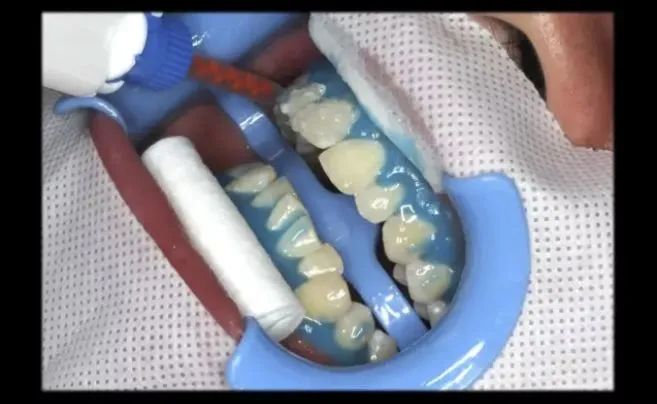

步骤很简单。我在征求病人的同意之后,采集了治疗全过程的照片来给大家演示一下!

开口护眼:可以让病人保持持续开口且不累,并防止眼睛被强光照射。

清理牙面:细致的牙面抛光、喷砂。

牙龈保护:非常重要!牙龈和牙齿边缘涂上隔离材料,避免氧化剂直接接触牙龈组织。

图片来源:作者拍摄

▎关键步骤

首先在牙齿的表面上涂上「美白剂」(过氧化氢凝胶)。当然,一般都涂前面的牙齿——因为后面的牙齿根本就看不到!